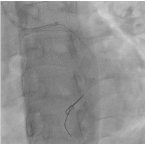

Trans-radial coronary angiogram revealed tortuous and aneurysmal dilatation (ectatic vessels) of all three major coronary arteries (Figure 3a, 3b) with huge thrombus in the proximal segment of left circumflex (LCx) artery, the culprit lesion was identified. Left coronary system was engaged with XB 3.0 6-French guiding catheter through right radial access with 6F sheath. The lesion was crossed by Run through NS floppy (Terumo) hydrophilic 0.014 inches wire. Among different strategies to deal with huge thrombus burden such as Plain Old Balloon Angioplasty (POBA), thrombus aspiration and intracoronary glycoprotein IIb/IIIa inhibitor, we proceeded with thrombus aspiration. Thrombuster II (Kaneka Corporation) thrombus aspiration catheter introduced into the target vessel and suctioning performed. Blood clots aspirated as shown (Figure 4). After few aspirations, failed to do further suctioning and planned to flush as the catheter may get blocked from aspirated thrombus. Some degree of resistance was felt while removing the catheter from the vessel. The thrombus aspiration catheter finally came out with slight pulling force but noted that the tip was missing (Figure 5). Angiographically, the tip of Thrombuster II catheter seen attached to the guidewire (Figure 6). The guidewire can move freely along the mid and distal LCx but failed to withdrawal at the proximal LCx area.

Figure 6. Broken thrombuster II catheter compared with new catheter